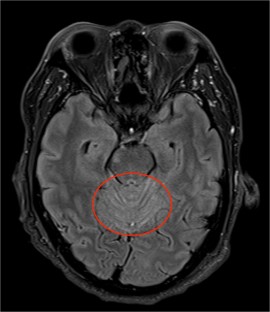

Fig. 2